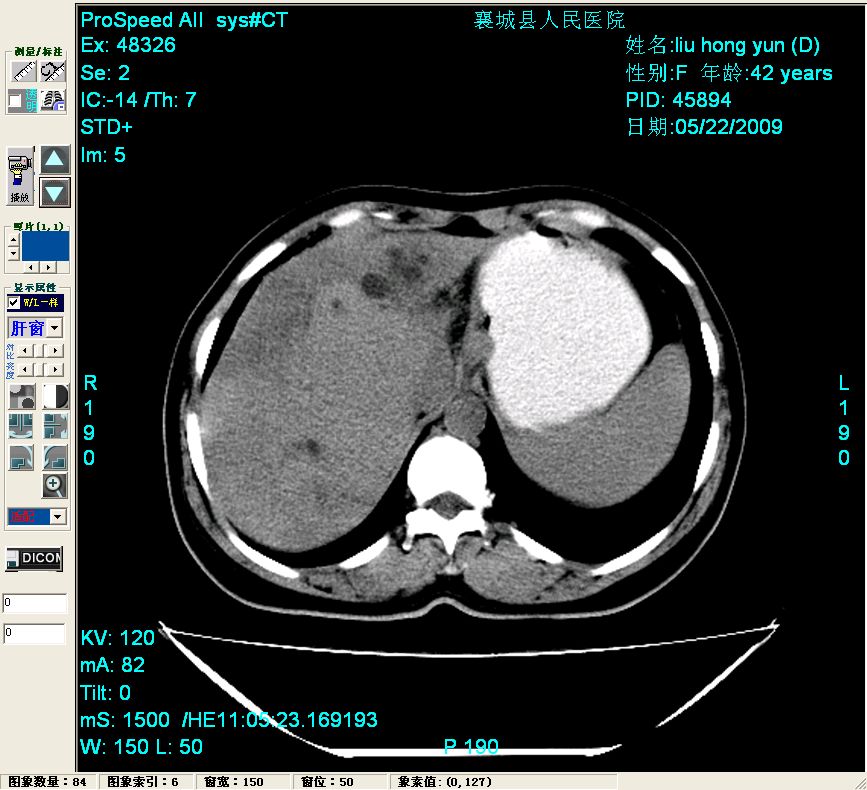

平扫:

平扫左肝外叶体积显著减小,左肝外叶见多房囊性低密度区,左肝实质及右肝前叶浅表实质呈低密度改变,左肝及右肝前叶胆管扩张,脾大

脂肪肝

胆管细胞癌可能性大

1)肝内胆管结石,胆总管末端结石伴肝内胆管扩张。2)肝左叶及肝右叶前段增强前后之异常表现,考虑炎性改变,不排除胆管细胞癌。